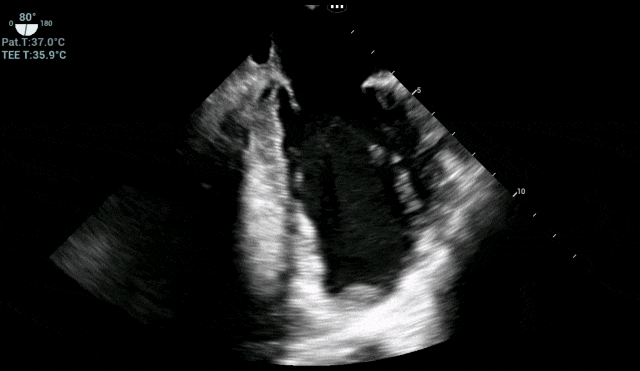

术中各时间段实时TEE监测心脏血栓情况

气腹与体位变动期:这是最易引起血压波动、心脏负荷变化的阶段。TEE实时显示心腔大小和收缩力的微妙变化,麻醉团队据此调整血管活性药物,将血压、心率牢牢控制在安全窗口内。

手术关键操作期:TEE始终锁定左心室,确认血栓无任何移位或脱落迹象,为外科医生创造了安心操作的环境。